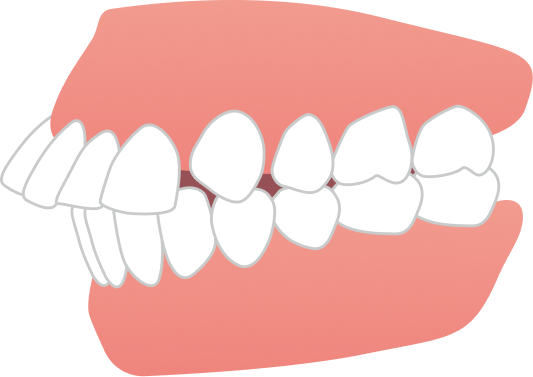

治療は、マウスピース矯正インビザラインにて矯正治療を行い、歯列全体のバランスと噛み合わせを考慮しながら計画を立てました。抜歯を行うことなく治療を進め、治療期間は2年10ヶ月で歯並びが整っています。

自然な見た目を保ちながら、無理なく歯並びを改善することができた症例です。

AFTER